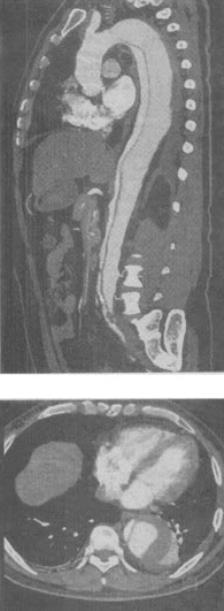

3、 患者,男,57岁,有冠心病史。突感胸背部剧痛,向腹部放射,行CT检查,如图,应诊断为()。

- A、真性胸动脉瘤

- B、假性胸动脉瘤

- C、主动脉夹层DeBakeyⅠ型

- D、主动脉夹层DeBakeyⅡ型

- E、主动脉夹层DeBakeyⅢ型